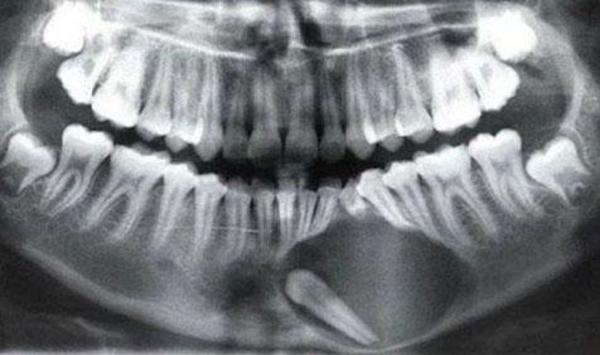

[/userfiles/files/kaz15.jpg]Many occurrences of supernumerary teeth on the mandibula of one patient and a similar condition in the maxilla of another patient. Abnormalities of the number and shape of tooth roots